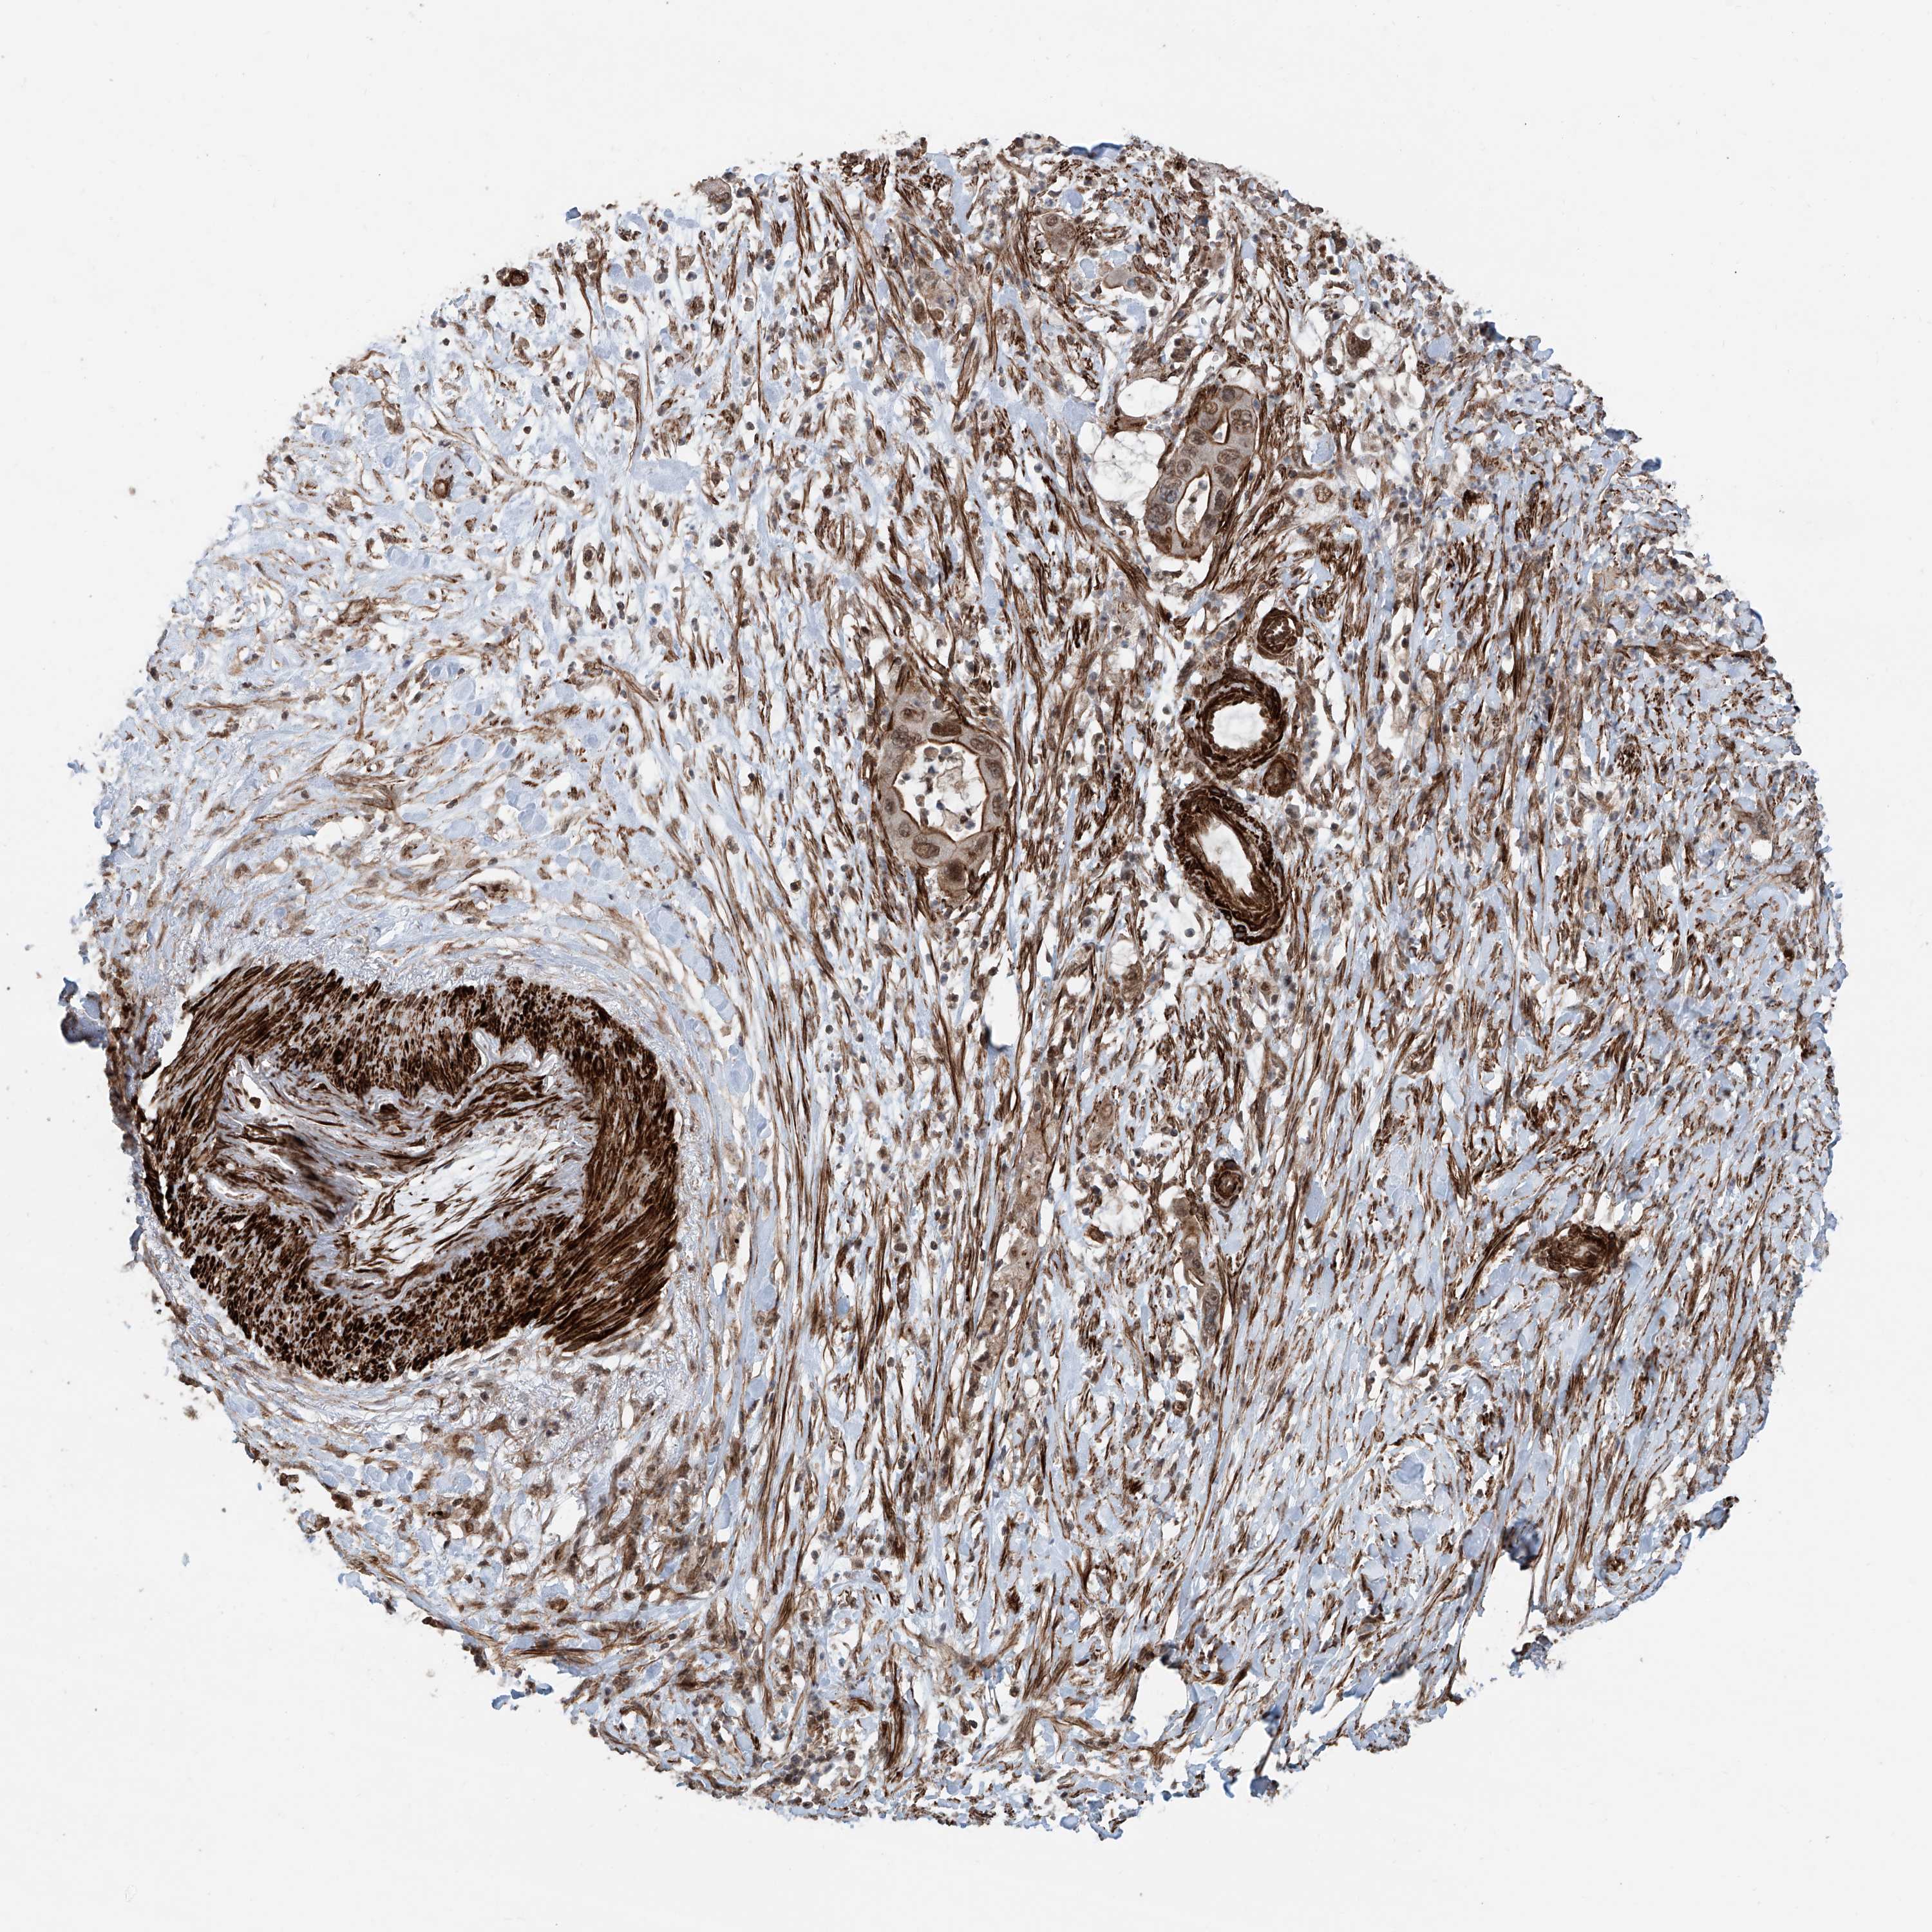

PANCREATIC CANCER - Protein expressioni

A mouse-over function shows sample information and annotation data. Click on an image to view it in a full screen mode. Samples can be filtered based on level of antibody staining by selecting one or several of the following categories: high, medium, low and not detected. The assay and annotation is described here.

Note that samples used for immunohistochemistry by the Human Protein Atlas do not correspond to samples in the TCGA dataset.

Antibody stainingi

Antibody staining in the annotated cell types in the current human tissue is reported as not detected, low, medium, or high, based on conventional immunohistochemistry profiling in selected tissues. This score is based on the combination of the staining intensity and fraction of stained cells.

Each image is clickable and will lead to virtual microscopy that enables deeper exploration of all samples and also displays staining intensity scores, fraction scores and subcellular localization as well as patient and tissue information for each sample.

Antibody HPA028467

Antibody HPA031255

Antibody HPA031256

Staining

High

Medium

Low

Not detected

Intensity

Strong

Moderate

Weak

Negative

Quantity

>75%

75%-25%

<25%

None

Location

Nuclear

Cytoplasmic/membranous

Cytoplasmic/membranous,nuclear

Adenocarcinoma, NOS